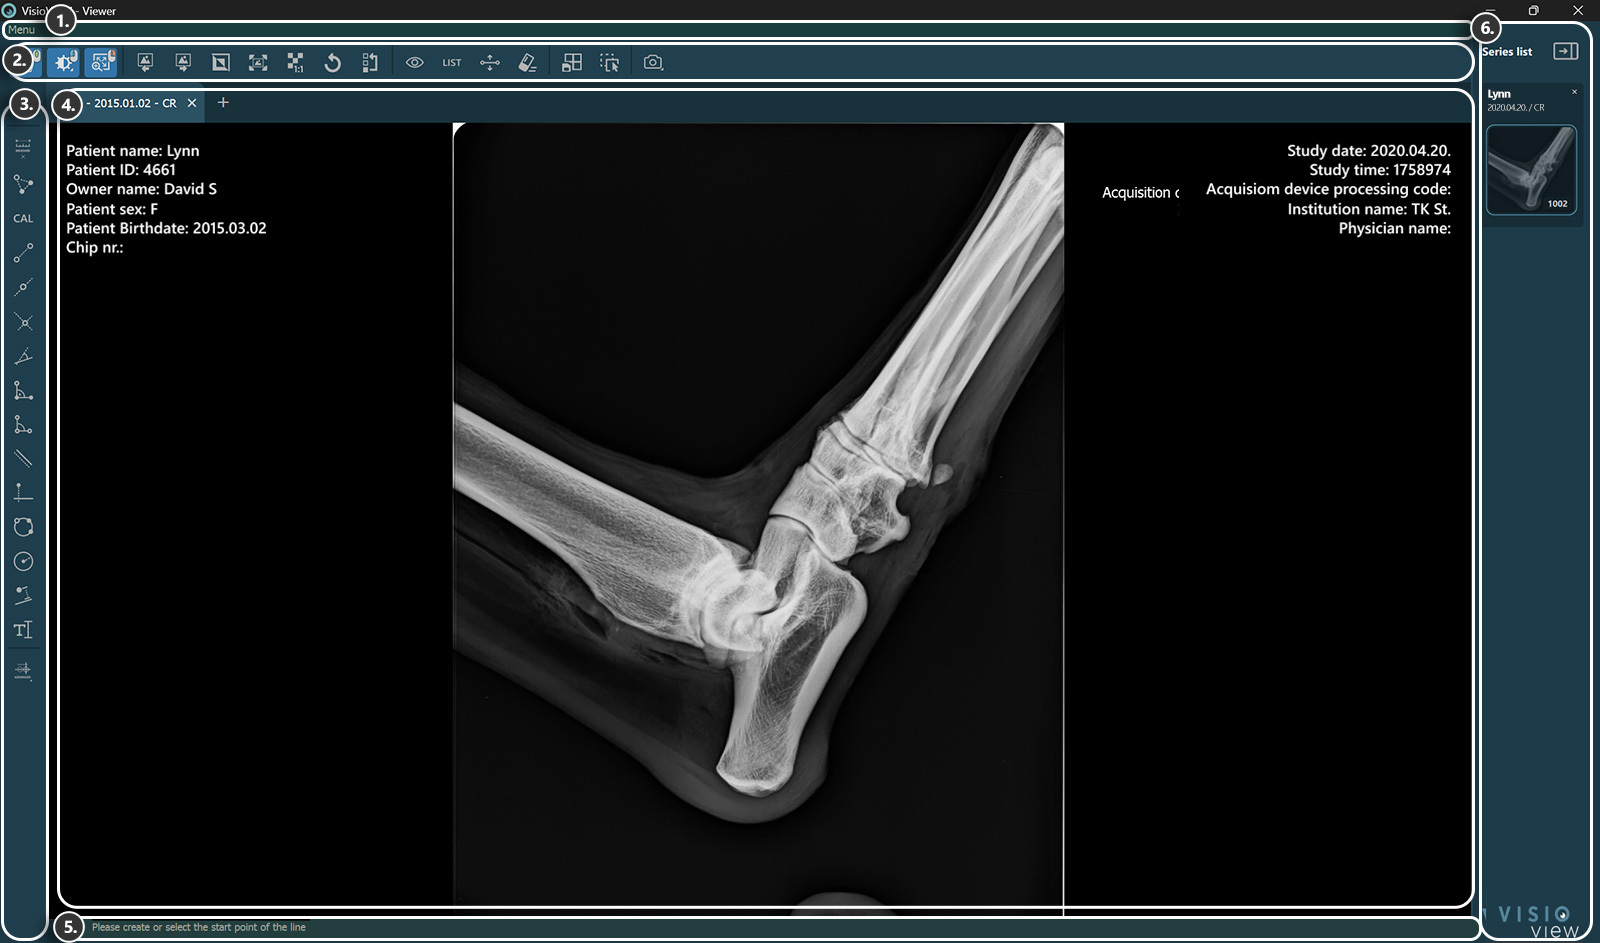

VisioVIEW – Viewer¶

Der VisioVIEW-Viewer ist ein spezialisierter DICOM-Viewer, der in der Lage ist, 2D-monochrome und farbige DICOM-Bilder darzustellen. Es unterstützt sowohl statische DICOM-Bilder als auch dynamische Sequenzen von Frames und Schichten. Zusätzlich unterstützt der VisioVIEW-Viewer MPEG-2-/MPEG-4-komprimierte Videodateien mit speziellen Videowiedergabesteuerungen.

Der VisioVIEW-Viewer wurde mit dem Ziel entwickelt, DICOM Hanging Protocols zu unterstützen, und nutzt eine Rasteransichtsfunktion, die es den Benutzern ermöglicht, den aktiven Tab in dedizierte Ansichten zu unterteilen, um ein individuell angepasstes Erlebnis zu bieten. Schließlich bietet es eine 2D-Multiplan-Rekonstruktion (MPR) volumetrischer Daten, die es den Benutzern ermöglicht, frei zwischen den verfügbaren Ebenen (Axial, Koronal und Sagittal) zu wechseln.

Der VisioVIEW-Viewer bietet zudem ein umfassendes Set an Werkzeugen für Anpassungen Bildmanipulationen sowie einfache und erweiterte Messungen und unterstützt somit die Diagnostik von Patienten. Die Kernfunktionen des VisioVIEW-Viewers sind über seine Benutzeroberfläche zugänglich:

Abschnitte des VisioVIEW-Viewers¶

Der VisioVIEW-Viewer besteht aus mehreren Abschnitten, die jeweils einem bestimmten Zweck dienen.

Viewer-Bereich¶

Patienteninformationen

Studieninformationen

Informationsleiste¶

Zeigt Informationen oder Anweisungen zum aktuell ausgewählten Werkzeug an.